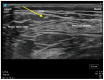

The incidence of hip fractures has continued to increase as life expectancy increases. Hip fracture is one of the leading causes of increased morbidity and mortality in the geriatric population. Early surgical treatment (<48 h) is often recommended to reduce morbidity/mortality. In addition, adequate pain management is crucial to optimize functional recovery and early mobilization. Pain management often consists of multimodal therapy which includes non-opioids, opioids, and regional anesthesia techniques. In this review, we describe the anatomical innervation of the hip joint and summarize the commonly used peripheral nerve blocks to provide pain relief for hip fractures. We also outline literature evidence that shows each block's efficacy in providing adequate pain relief. The recent discovery of a nerve block that may provide adequate sensory blockade of the posterior capsule of the hip is also described. Finally, we report a surgeon's perspective on nerve blocks for hip fractures.

Keywords: fascia iliaca block; lateral femoral cutaneous nerve; pericapsular nerve group (PENG) block.